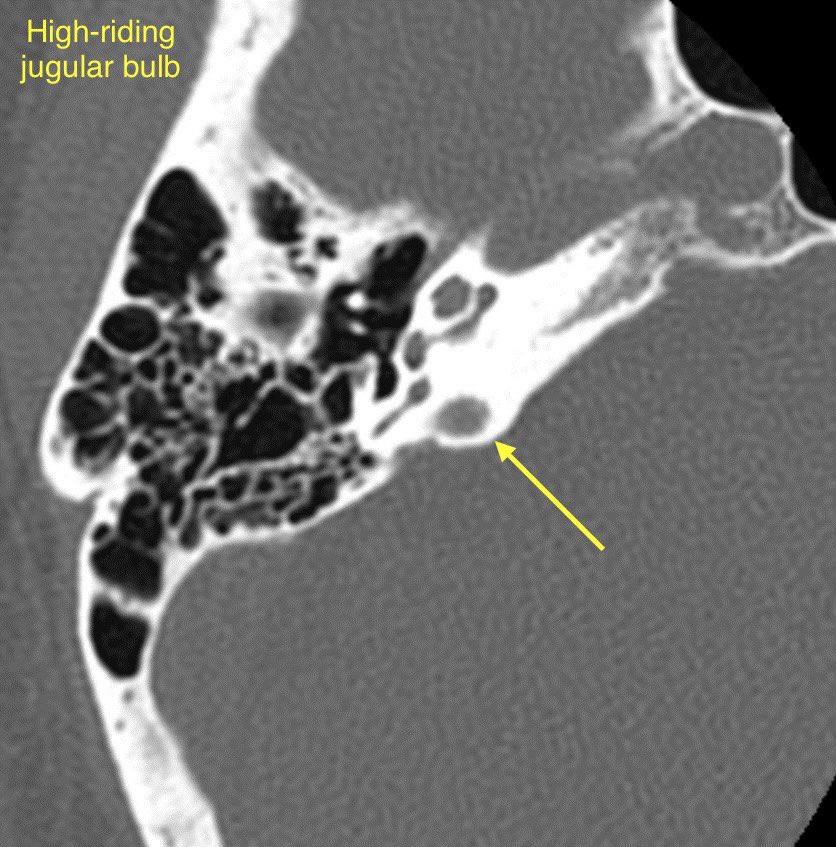

🔷JUGULAR BULB ABNORMALITIES

1️⃣High-riding jugular bulb

2️⃣Jugular bulb dehiscence

🔹High-riding jugular bulb is associated with jugular bulb dehiscence

💡"High" = within 2mm of the floor of the IAC, above the lower border of the round window, above the posterior semicircular canal, or above the basal turn of the cochlea

🔹Jugular bulb dehiscence: Thinning or visible defect of the jugular plate